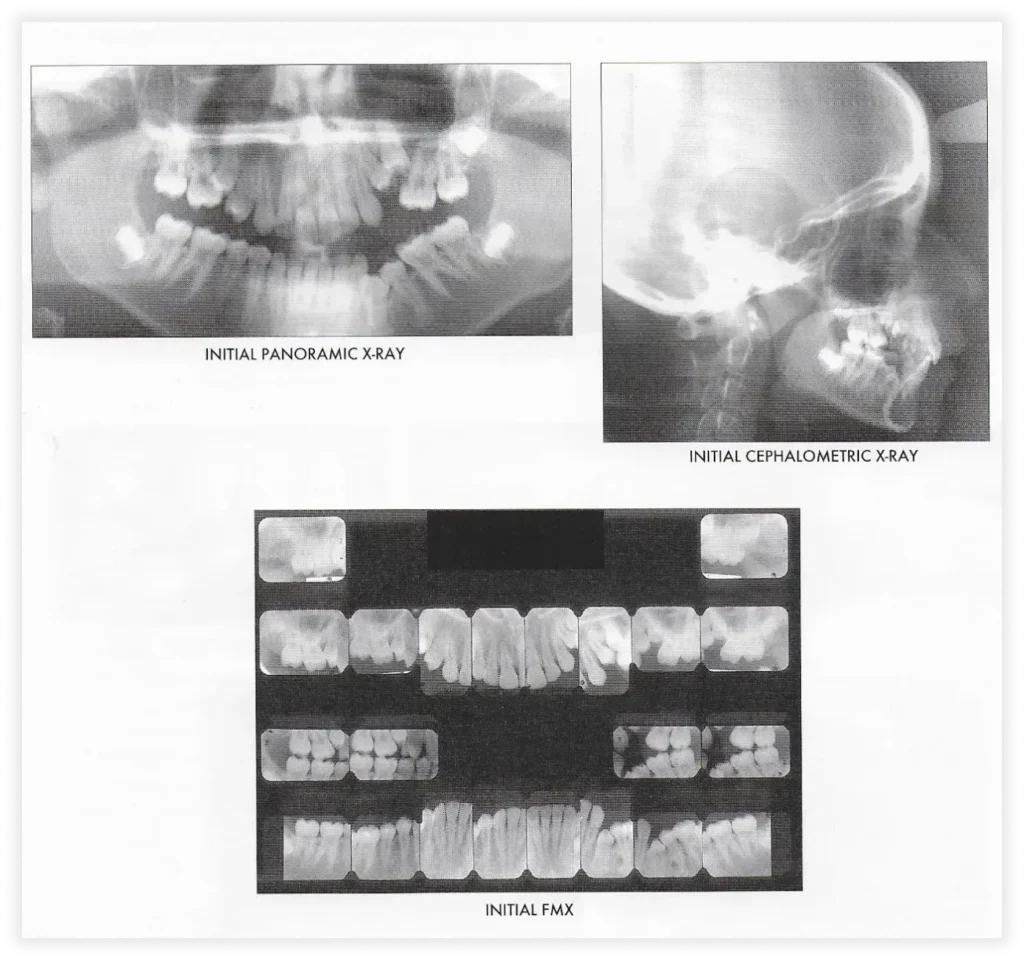

Smile Gallery

Take a look at some of our cases and successful transformations below.

Case #1

Initial Photos